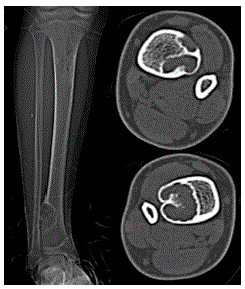

Criança levada a emergência por trauma na tíbia em jogo de futebol.

Baseado na imagem disponibilizada, qual o seu diagnóstico?